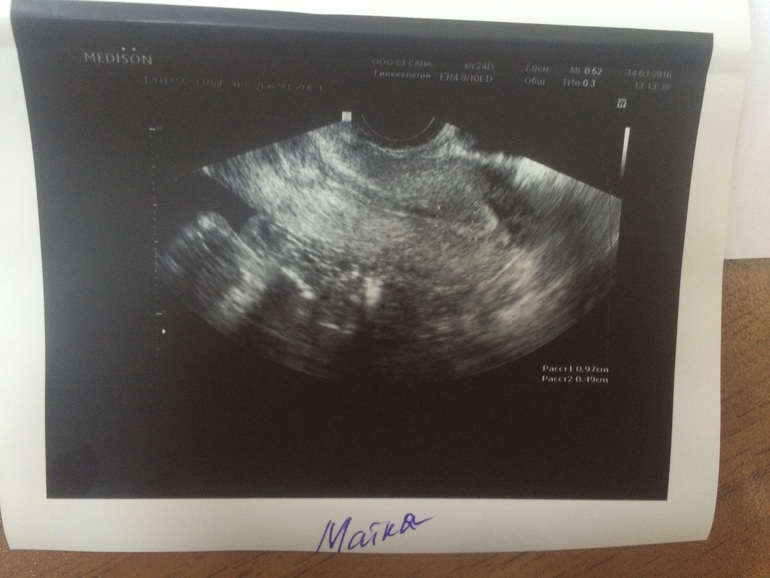

Сходила сегодня (в продолжение моих печалек отрицательный тест) на узи (14 дц) иииии...... (под кат)

Там ЖТ 21*18

это первое фото ЖТ в моем дневнике (аппарат узи совсем не хороший поэтому на фото плохо видно, но мне на экране показали его хорошо) моей радости небыло предела. Эндик 9,7 (в хвасте 4,9 мм)

Да жидкость есть )) на экране она мне показала все рассказала ... там ЖТ прям как на картинке, я такого никогда в живую не видела ))) она сказала добавить дюф, т.к. ее немного смущает мой эндометрий )) вообщем сказала приходить после задержки )) очень жду и верю )